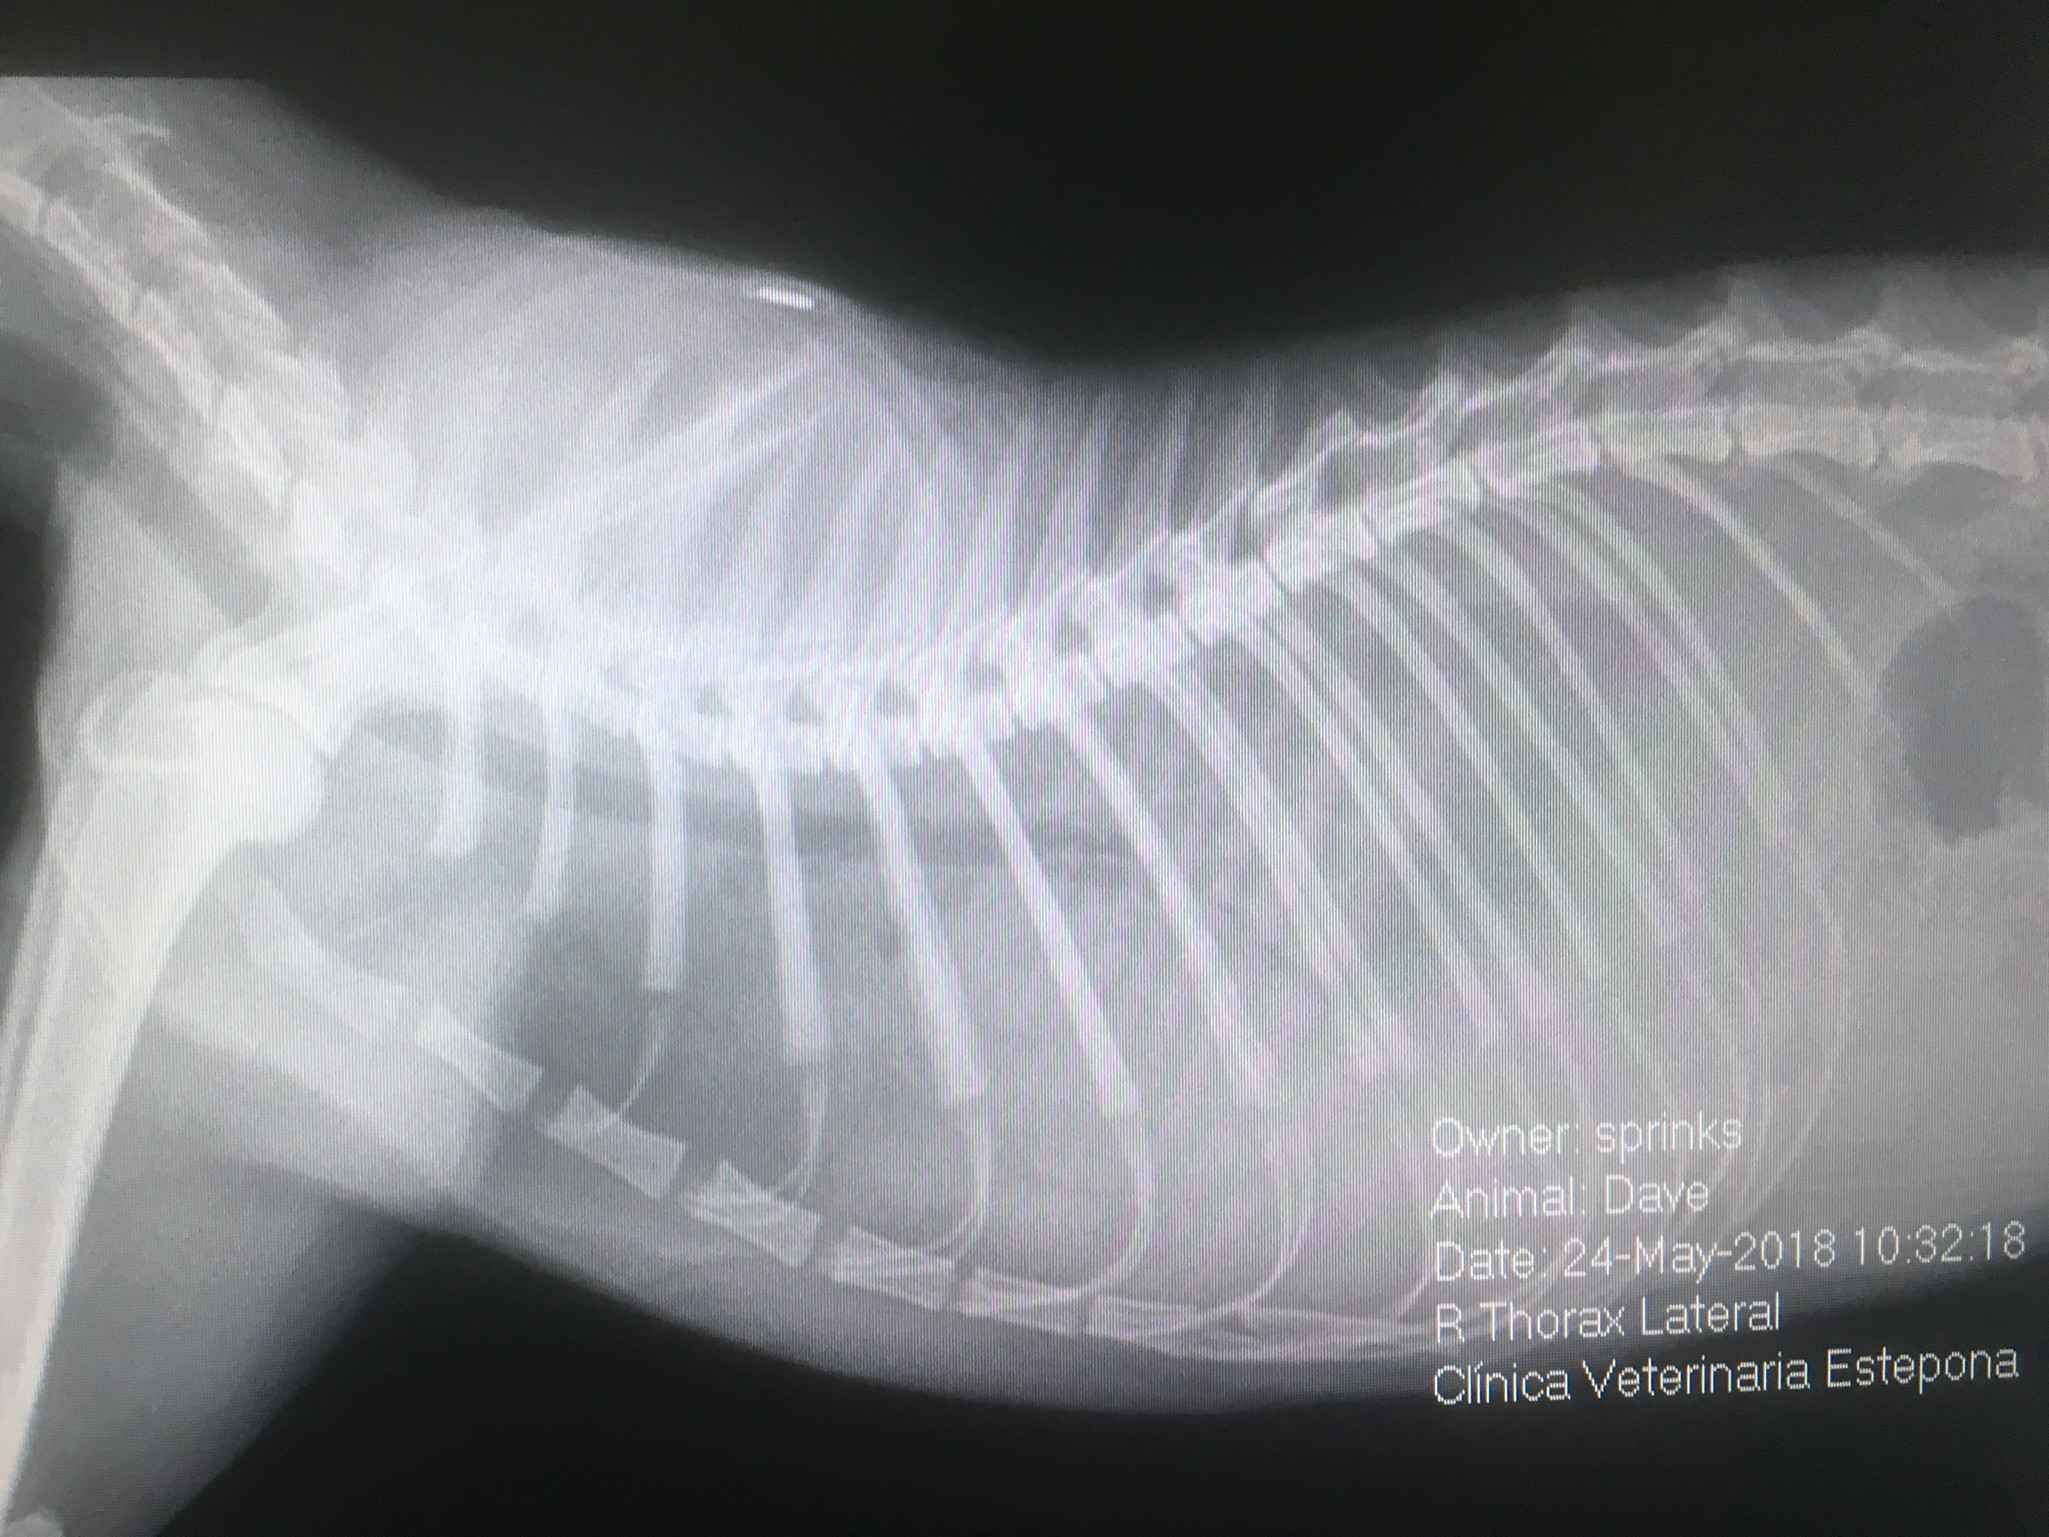

Rentgenografia (RTG) jest integralną częścią medycyny weterynaryjnej, stosowana nie tylko w przypadku diagnozowania układu kostnego, ale również może służyć do badania serca, płuc i narządów jamy brzusznej. Można wykonać zaawansowane procedury, takie jak radiografia kontrastowa (cystografia do oceny pęcherza moczowego, urografia do oceny nerek, mielografia do oceny rdzenia kręgowego, kontrastowe badanie żołądkowo-jelitowe) i radiografia pozycyjna.

Radiografia cyfrowa zrewolucjonizowała medycynę ludzką i weterynaryjną ze względu na jej wygodę i poprawę szczegółowości tkanek miękkich. Dzieki niej uzyskujemy doskonałą jakość obrazu, a uzyskane rentgenogramy cyfrowe są natychmiast dostępne dla lekarza co zdecydowanie skraca czasu zabiegu.